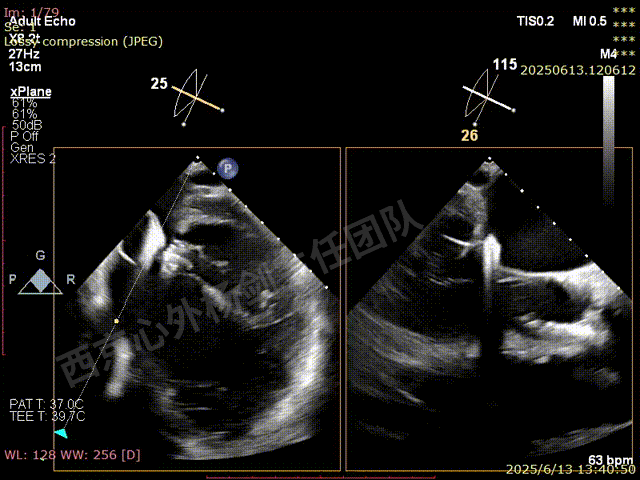

TAVR术后,全心增大,二尖瓣反流重度,三尖瓣反流重度。中量心包积液。左室严重增大,标准图像调整困难。主动脉瓣位带支架人工瓣膜瓣叶启闭正常,主动脉瓣位人工瓣上血流速度Vmax 148cm/s,PGmax 9mmHg,Vmean 86cm/s,PGmean 2mmHg, VTI 34.7cm,瓣周反流(轻)。估测肺动脉收缩压约49mmHg;左室收缩功能明显减低。LVEF:23%,EDV:364ml,ESV:221ml。

彩色血流示:二尖瓣反流缩流颈彩宽6.6mm,面积17cm²,容积30ml;二尖瓣瓣口面积6.6cm²,瓣环内径:左右径34mm,前后径34mm。2区瓣叶长度:前叶36mm,后叶20mm,叶环比1.6. 三尖反流面积17.2cm²,容积33ml,Vmax 291cm/s,PGmax 34mmHg。